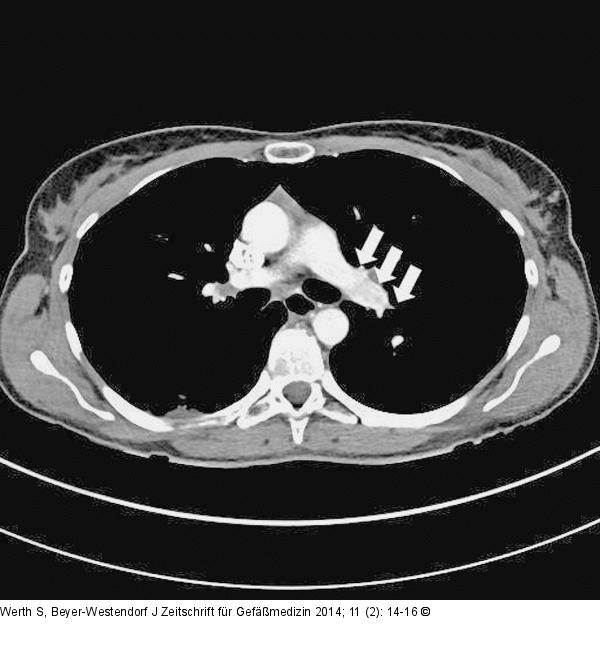

Abbildung 3: Verlaufskontrolle CT-Verlaufskontrolle nach 6 Monaten mit nun freier zentraler pulmonalarterieller Strombahn (Pfeile). |

CT-Verlaufskontrolle nach 6 Monaten mit nun freier zentraler pulmonalarterieller Strombahn (Pfeile). |